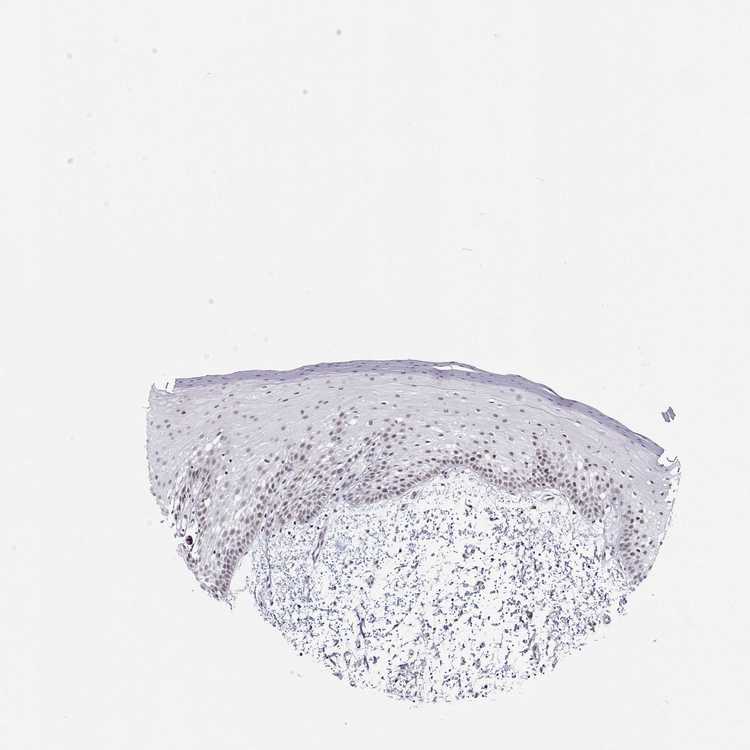

TISSUE PRIMARY DATA ORAL MUCOSA Show tissue menu

ORAL MUCOSA - Antibody stainingi

Antibody staining in the annotated cell types in the current human tissue is reported as not detected, low, medium, or high, based on conventional immunohistochemistry profiling in selected tissues. This score is based on the combination of the staining intensity and fraction of stained cells.

Each image is clickable and will lead to virtual microscopy that enables deeper exploration of all samples and also displays staining intensity scores, fraction scores and subcellular localization as well as patient and tissue information for each sample.

Antibody HPA061693

Squamous epithelial cells Low